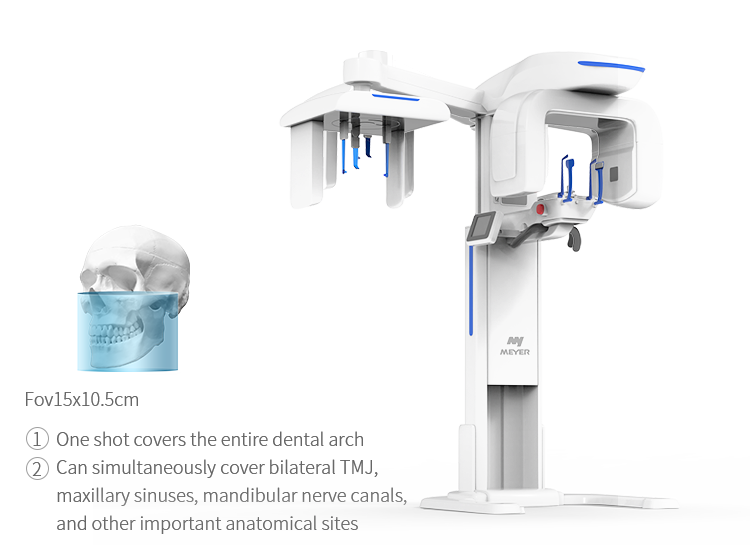

- Amplio campo de visión, satisfaciendo las necesidades clínicas generales.